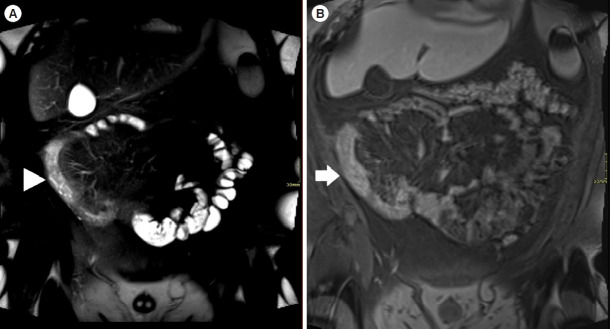

Background/aims: Assessment of quality of magnetic resonance enterography (MRE) in small bowel Crohn's disease (CD) activity evaluation has received little attention. We assessed the impact of bowel distention and motion artifact on MRE activity indices in ileal CD.

Methods: A cohort of patients who underwent contemporaneous MRE and colonoscopy for ileal CD assessment between 2014 and 2021 at 2 centers were audited. An abdominal radiologist blinded to clinical data reviewed each MRE, graded bowel distention and motion artifact upon a pre-specified 3-point scale and calculated the original magnetic resonance index of activity (MaRIA) and simplified MaRIA (sMaRIA), London index and CD MRE index (CDMI). Ileal endoscopic activity was graded via the Simplified Endoscopy Score for CD (SES-CD). The performance of MRE indices in discriminating active disease (SES-CD ≥3) stratified by MRE quality was measured by receiver operator characteristic analyses.

Results: One hundred and thirty-seven patients had MRE and colonoscopy within a median of 16 days (range, 0-30 days) with 63 (46%) exhibiting active disease (SES-CD ≥3). Forty-four MREs (32%) were deemed low quality due to motion artifact and/or moderate to poor distention. Low-quality MREs demonstrated reduced discriminative performance between ileal SES-CD ≥3 and MRE indices (MaRIA 0.838 vs. 0.634, sMaRIA 0.834 vs. 0.527, CDMI 0.850 vs. 0.595, London 0.748 vs. 0.511, P<0.05 for all). Individually the presence of any motion artifact markedly impacted the discriminative performance (e.g., sMaRIA area under the curve 0.544 vs. 0.814, P<0.05).

Conclusions: Image quality parameters can significantly impact MRE disease activity interpretation. Quality metrics should be reported, enabling cautious interpretation in lower-quality studies.